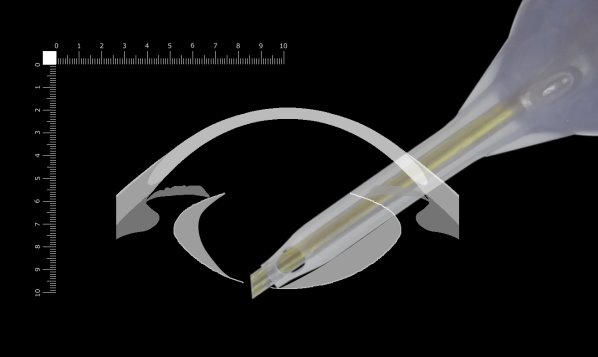

ここでは側面画像から考えます。

手術顕微鏡で眼内を見るとき、ほとんど立体視はできないと言われています。一番深い辺りでは掘っている深さがよく分からなくなることがあります。チップのベベルが垂直より向こう(下)を向いている場合、実際に掘っているところは見えません。そして突き抜けると破嚢してしまうことがあります。